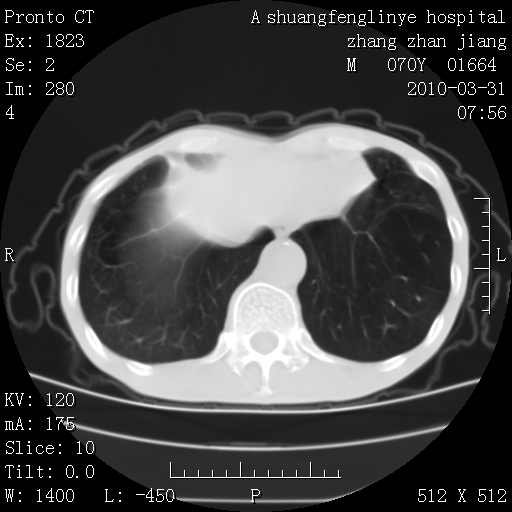

标题: CT25450:肺结核?

双上肺继发型tb并左上空洞形成,主动脉冠脉钙化。

支持:继发性肺结核伴空洞形成!建议纤支镜检查待出外周围型肺癌可能!

1)两肺上叶继发性肺结核并左肺上叶空洞形成。2)冠状动脉及主动脉钙化。